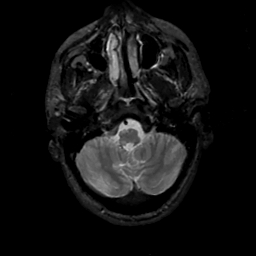

MR Study #14, June 2, 1991 -- Slice #8

[Home][Help][Clinical][Tour 1][Tour 2] Slice 8